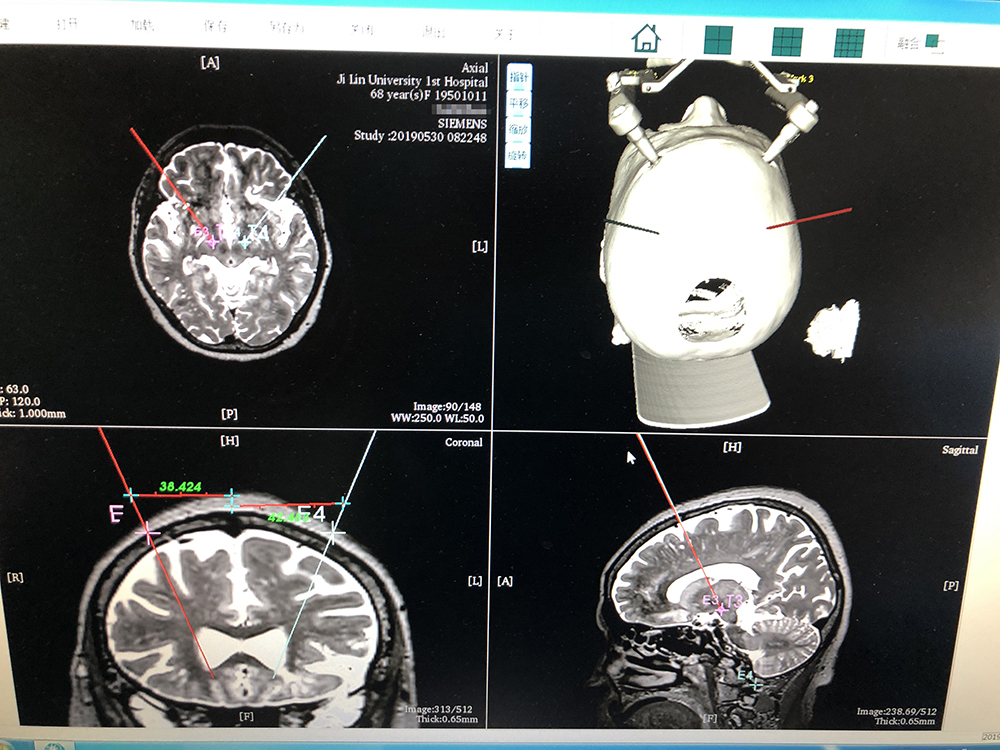

術前,邱吉慶教授借助“睿米”神經外科手術機器人配套軟件,為患者制定雙側 STN 核團植入電極的手術路徑規(guī)劃。

借助“睿米”軟件制定手術規(guī)劃